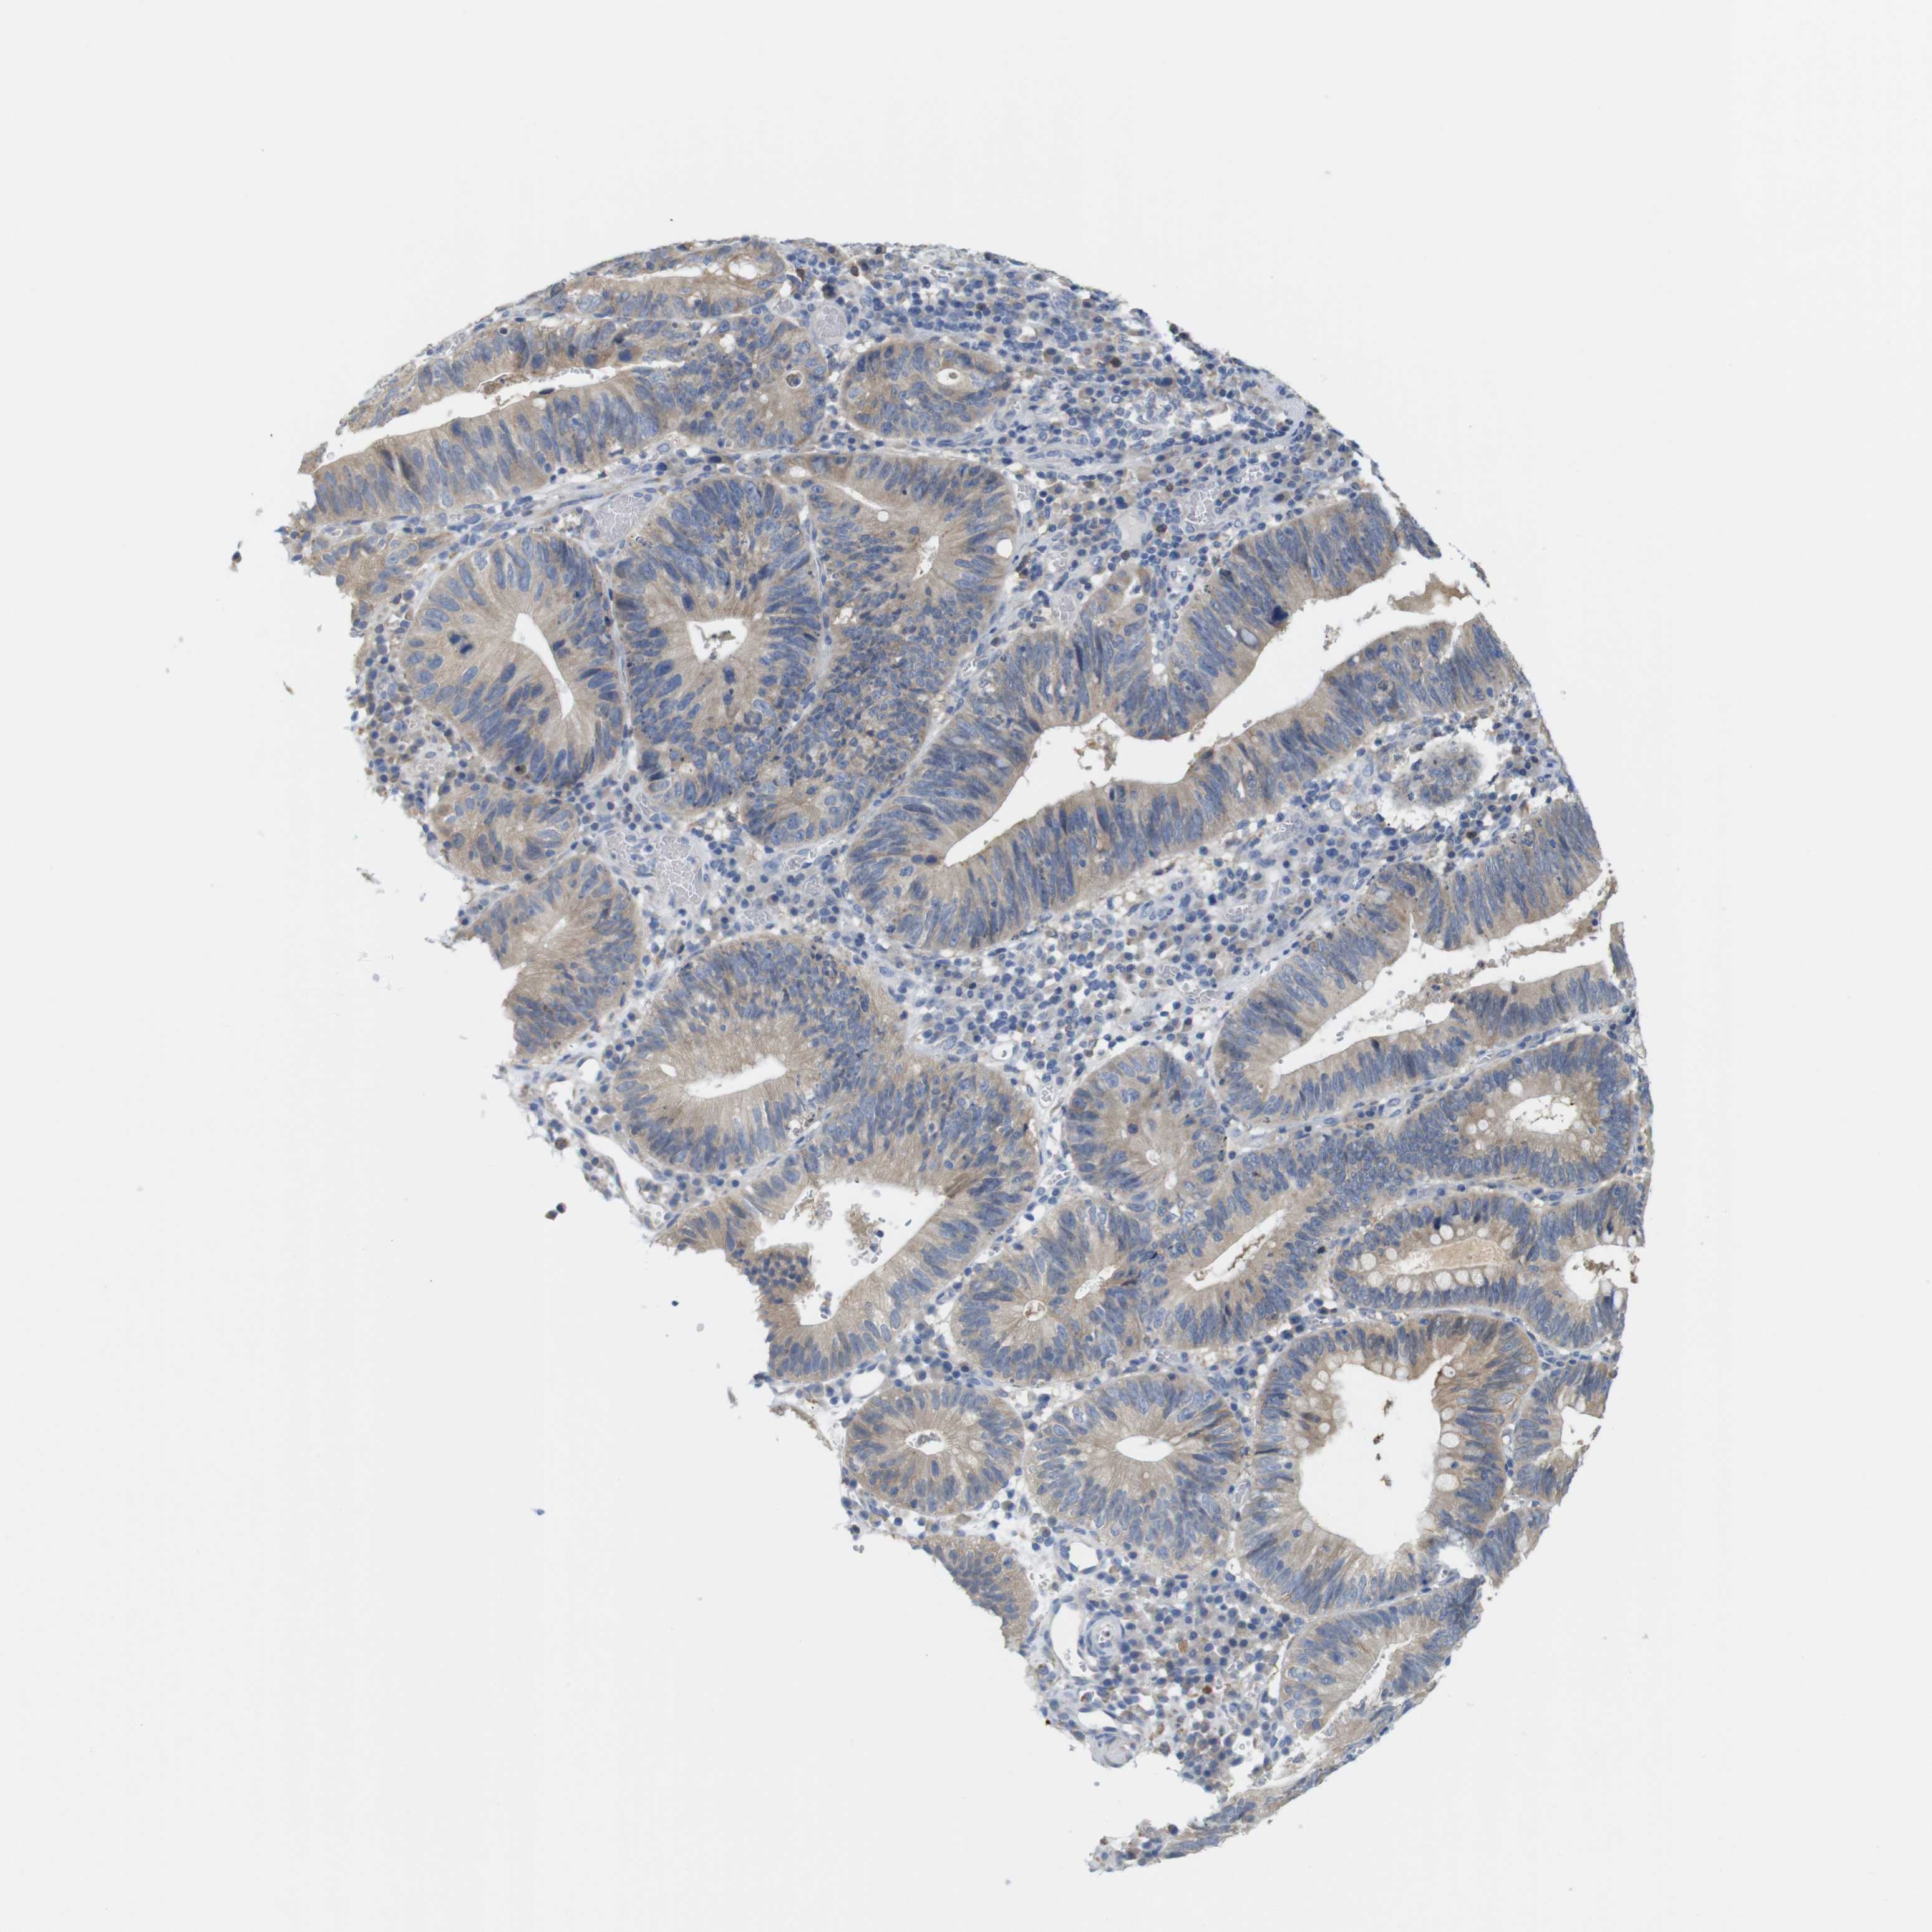

STOMACH CANCER - Protein expressioni

A mouse-over function shows sample information and annotation data. Click on an image to view it in a full screen mode. Samples can be filtered based on level of antibody staining by selecting one or several of the following categories: high, medium, low and not detected. The assay and annotation is described here.

Antibody stainingi

Antibody staining in the annotated cell types in the current human tissue is reported as not detected, low, medium, or high, based on conventional immunohistochemistry profiling in selected tissues. This score is based on the combination of the staining intensity and fraction of stained cells.

Each image is clickable and will lead to virtual microscopy that enables deeper exploration of all samples and also displays staining intensity scores, fraction scores and subcellular localization as well as patient and tissue information for each sample.

Antibody HPA013994

Antibody HPA013995

Staining

High

Medium

Low

Not detected

Intensity

Strong

Moderate

Weak

Negative

Quantity

>75%

75%-25%

<25%

None

Location

Nuclear

Cytoplasmic/membranous

Cytoplasmic/membranous,nuclear

Adenocarcinoma, NOS

Adenocarcinoma, High grade